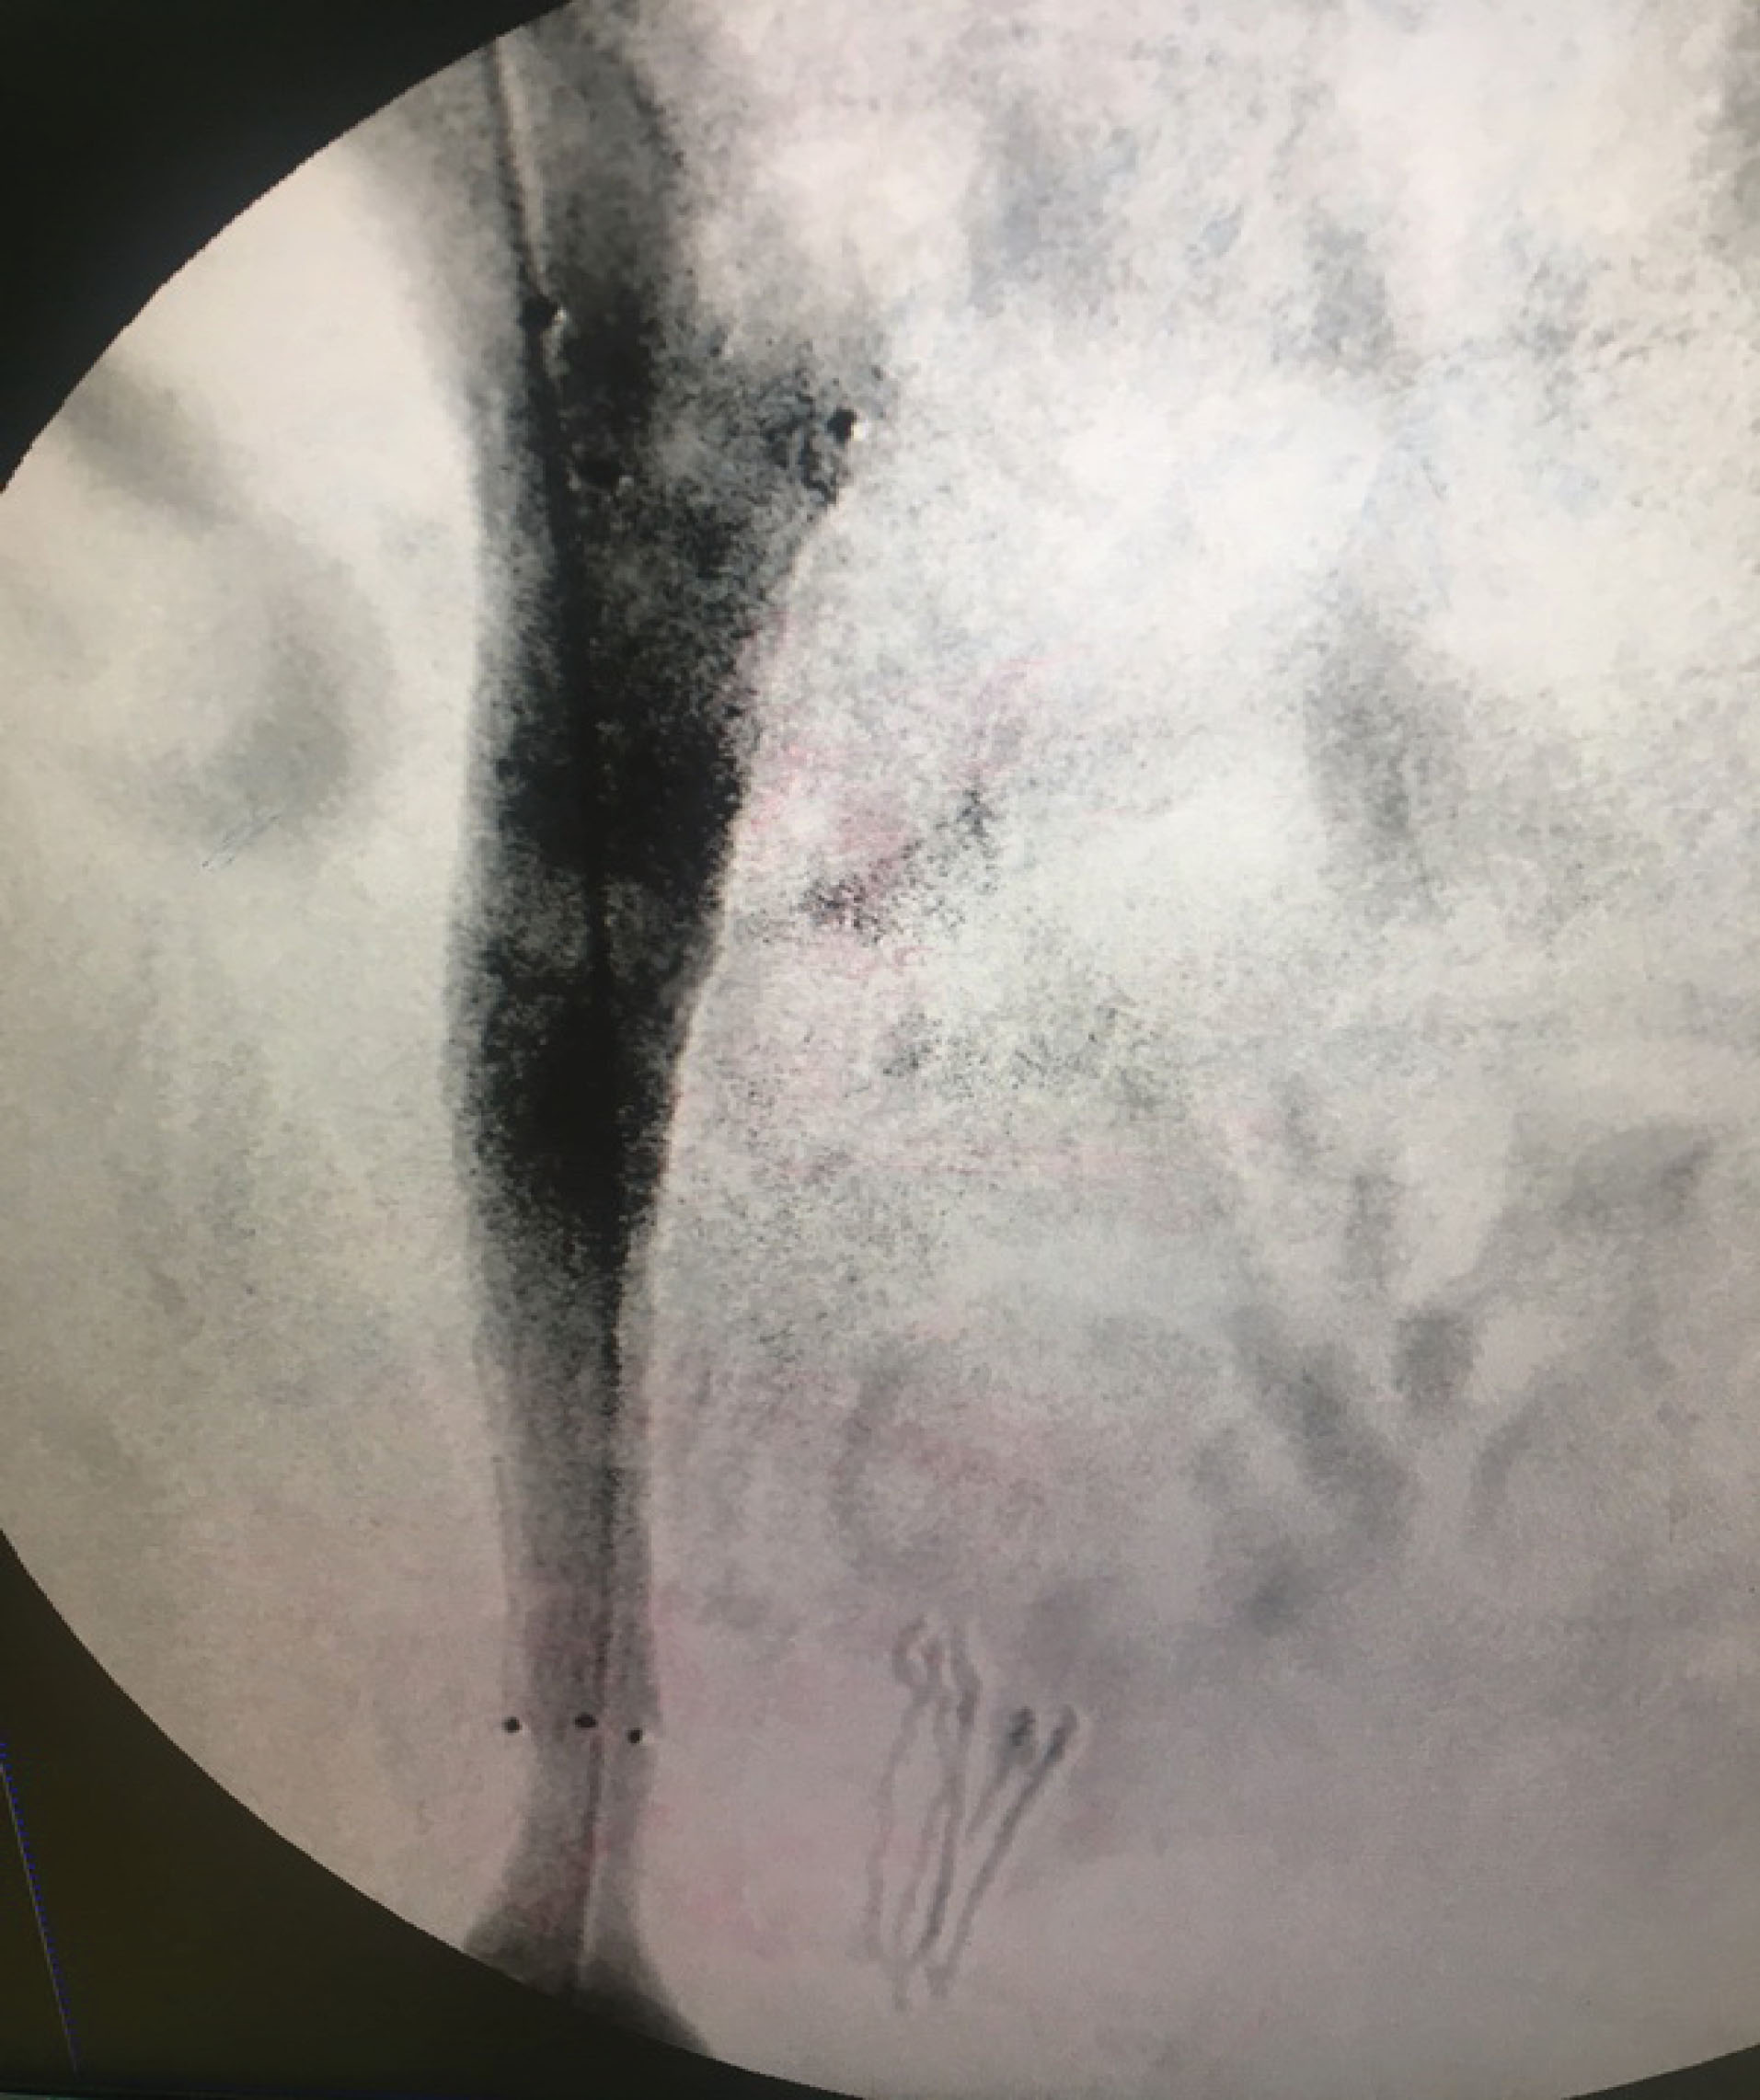

We did venography to reveal the underlying cause of venous stasis in right lower extremity. We did the imaging on prone position. A 5F sheath was introduced through the right popliteal vein. The external iliac vein had severe stenosis and invasion of pelvic mass into the vein was evident. This procedure was done under close monitoring of vital signs and local anesthesia. We transformed the patient to supine position to cannulate right superficial femoral vein (SFV). An 8F sheath was introduced into SFV by ultrasound guidance and Seldinger technique 10cm below the inguinal ligament. The reason for changing the position of the patient was that the procedure of stenting is painful. We wanted to do the procedure under deep sedation and it was not possible to do this in prone position because of general condition of the patient. A repeat venogram was obtained at supine position and similar results were found (). Venography was repeated at 45 and 90 degrees of left lateral oblique views and severe stenosis and tumor invasion were confirmed. A 0.035 hydrophilic standard guidewire was introduced through the sheath and the stenosis was crossed. Then a 40 mm length and 10 mm diameter CONQUEST balloon (BARD) was introduced over the guidewire. Venoplasty of external iliac vein was conducted throughout the stenosis and at proximal and distal parts. Then a venous stent of 80 mm length and 12 mm diameter (VENOVO, BARD) was introduced over the guidewire and deployed in the external iliac vein with the stenosis trapped inside the length of the stent. The completion venogram illustrated dilatation of the stenosis and reestablishment of flow of contrast material through the external iliac vein (). Then a 40 mm length and 12 mm diameter CONQUEST balloon (BARD) was introduced over the guidewire. Balloon dilatation was done through the stent and its proximal and distal landing zones. 7500 units of intravenous heparin was administered during the procedure. A loading dose of 300mg Clopidogrel was administered to the patient after the procedure at the recovery theater. The patient was anticoagulated by heparin for 48 hours and Clopidogrel 75mg daily was also administered during that period. Rivaroxaban 10mg per 12 hours and Clopidogrel 75 mg daily was administered on discharge. The patient was on Aspirin 80 mg daily before the procedure and we advised him to continue the same dose.

jcvtr-13-84-g001

Figure 1. Severe stenosis of right external iliac vein secondary to compression from diffuse right pelvic mass